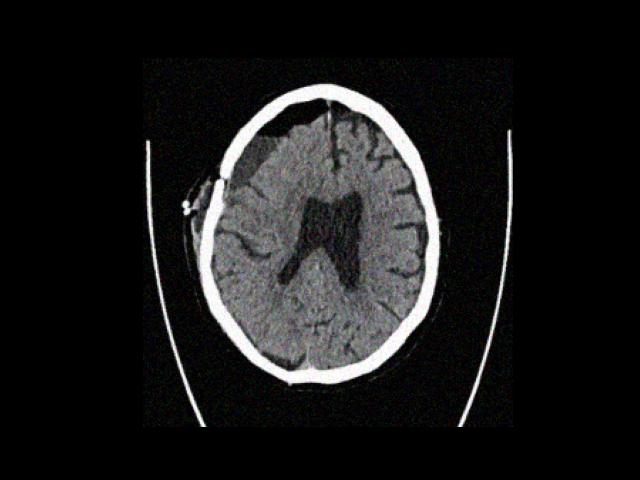

Sample Gallery